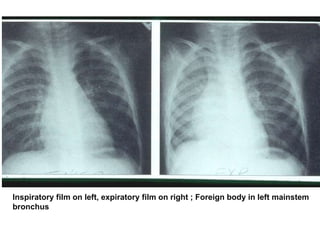

Inspiratory film on left, expiratory film on right ; Foreign body in left mainstem

bronchus

Chest X-ray forAspirated Foreign Bodies ƒ Foreign object radiopaque in 6 to 20 % ƒ CXR normal in 18 to 33 % ƒ CXR findings: –obstructive emphysema –atelectasis –pneumonia ƒ Expiratory film enhances CXR yield

Inspiratory film onleft, expiratory film on right ; Foreign body in left mainstem bronchus